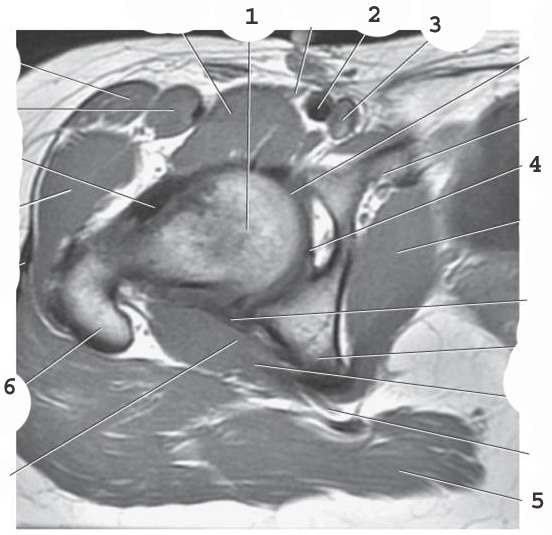

1

femoral head

2

femoral artery

3

femoral vein

4

ligamentum teres

5

gluteus muscles

6

greater trochanter